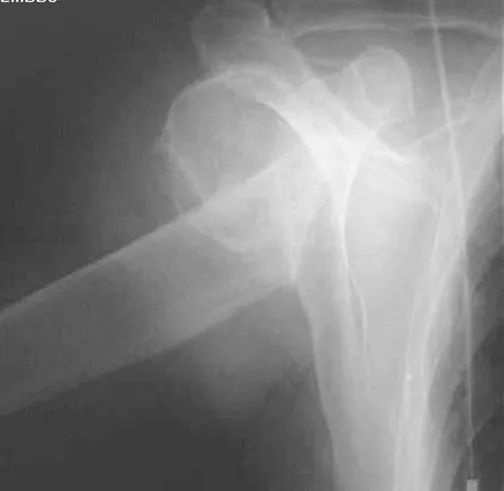

正常肩关节

肱骨外科颈骨折

内收或外展型损伤–最常见–骨折线为横行,伸展型损伤–间接外力引起–骨折线横行,向前成角,屈曲型损伤:较少见。